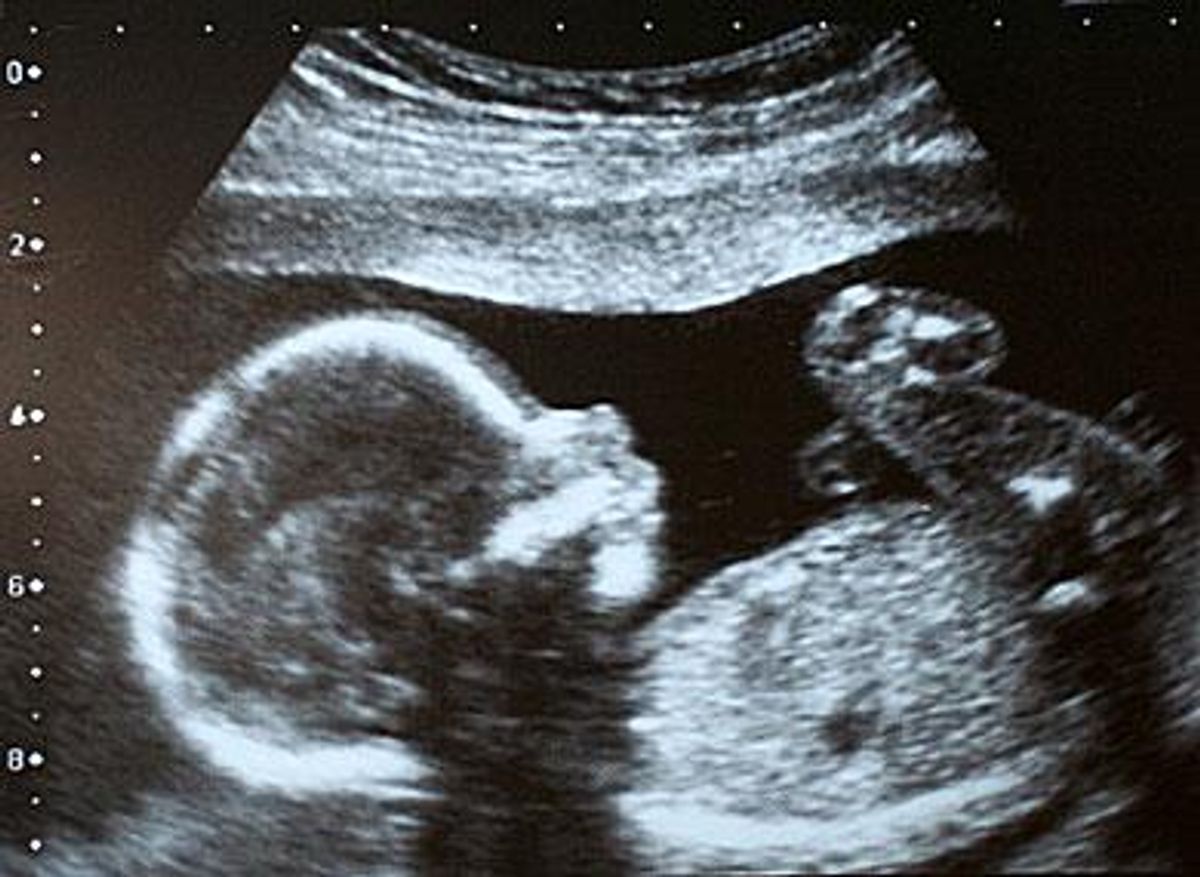

After a medical examination, he was released, and doctors reportedly said the pregnancy, now seven months along, will proceed normally.

Israeli Doctors Meet Pregnant Man